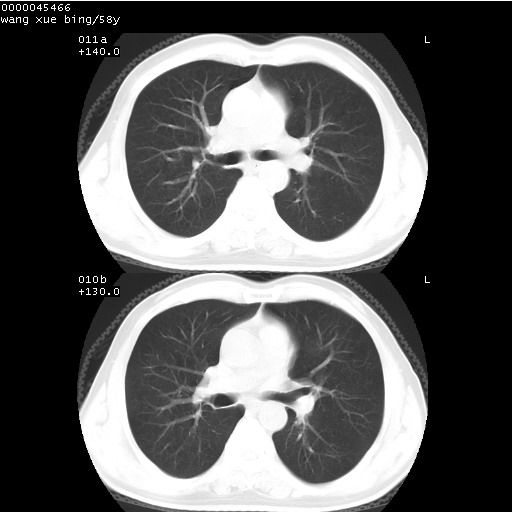

患者 男,58岁。咳嗽、咯血3月余。

胸部cr x线片提示:1)右下肺脓肿。2)右下肺周围型肺癌不排除。建议:行ct扫描检查。

胸部ct轴位平扫(层厚10mm,螺距1.5,重建间隔10mm),图像如下:

右肺下叶团块及不规则空洞,内壁不规则,外缘见粗长毛刺,临近胸膜明显增厚并与病灶关系密切。支持考虑:右肺肺脓肿!建议穿刺病理检查待除外周围型肺癌!

右肺下叶见不规则厚壁空洞,内壁不规则,外缘见粗长毛刺,临近胸膜明显增厚并与病灶关系密切。支持考虑:周围型肺癌!

右肺下叶周围型肺癌伴空洞形成!征象比较明显!分叶、毛刺、胸膜凹陷征、厚壁空洞,壁结节!

空洞壁厚,不规则,其内可见壁结节,周围可见毛刺及阻塞性炎变,多考虑癌性病变.

空洞内壁不规整,有壁结节,周围有毛刺,支持癌性空洞。